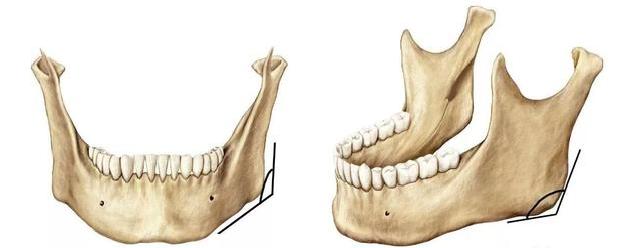

下颌角系下颌支后缘与下颌体下缘相交而成,其角度的大小与年龄及咀嚼力的大小有关。我们从侧面看下颌角的角度,一般较好的角度在120度左右,小于120度或约等于90度的,下颌角就会呈现方形或梯子型。

同时,下颌角到耳根的距离为1-2cm更为合适,能给面部增加一定的立体感,另外耳根点到下颌点的距离越长,脸会越方。严重者下颌角的宽度甚至超过了颧骨的宽度,这些都表示求美者的生理下颌角过大过宽,可以考虑通过下颌角手术来解决这些问题。